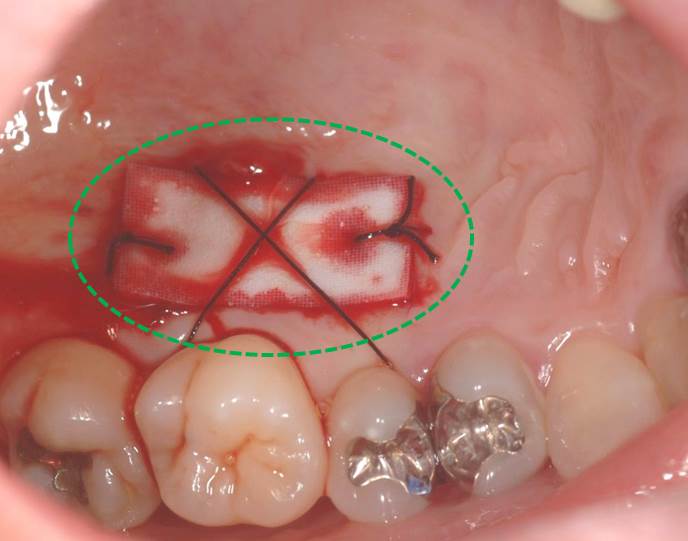

そして、上顎の裏側より、「動かない歯茎」を移植しました。

上顎裏側の緑○部分より移植し、創傷治癒材でカバーしています。